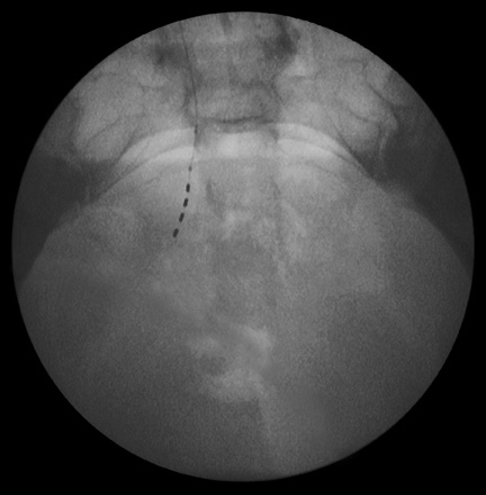

最終的なリード留置位置を確認

リード先端の方向が、尾側かつ外側を向いていることが望ましい。

側面像によるリード留置位置

正面像によるリード留置位置